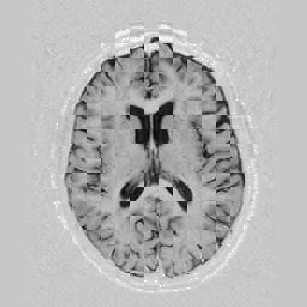

The results are shown for another pair of images in Figure [*].

Figure: Multi-scale NRR. From left to right, top then bottom: before NRR; after 5 iterations of NRR at level 2; after another 5 iterations of NRR at level 1.